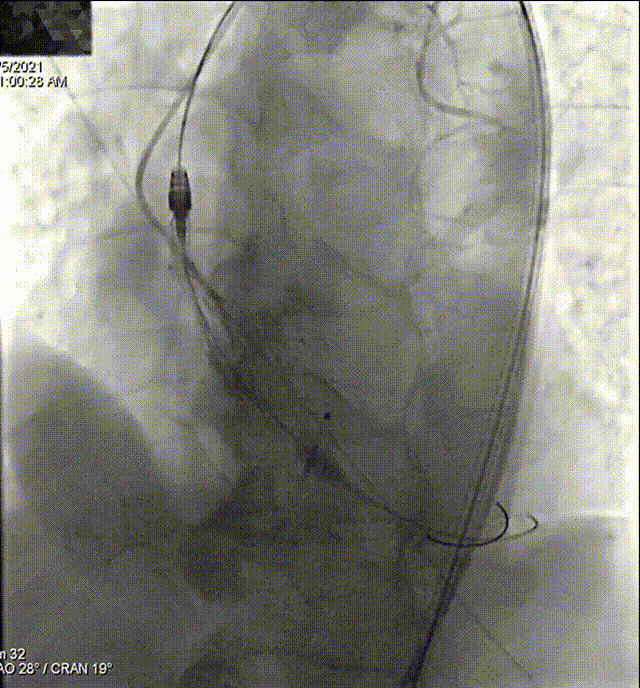

主动脉根部造影

Lunderquist导丝垮瓣

快速起搏下球囊预扩

瓣膜过弓、跨瓣

冒烟确认到达预期位置

160次/min快速起搏下完成瓣膜释放,植入24 mm VitaFlow瓣膜

180次/min快速起搏下22 mm球囊行后扩处理